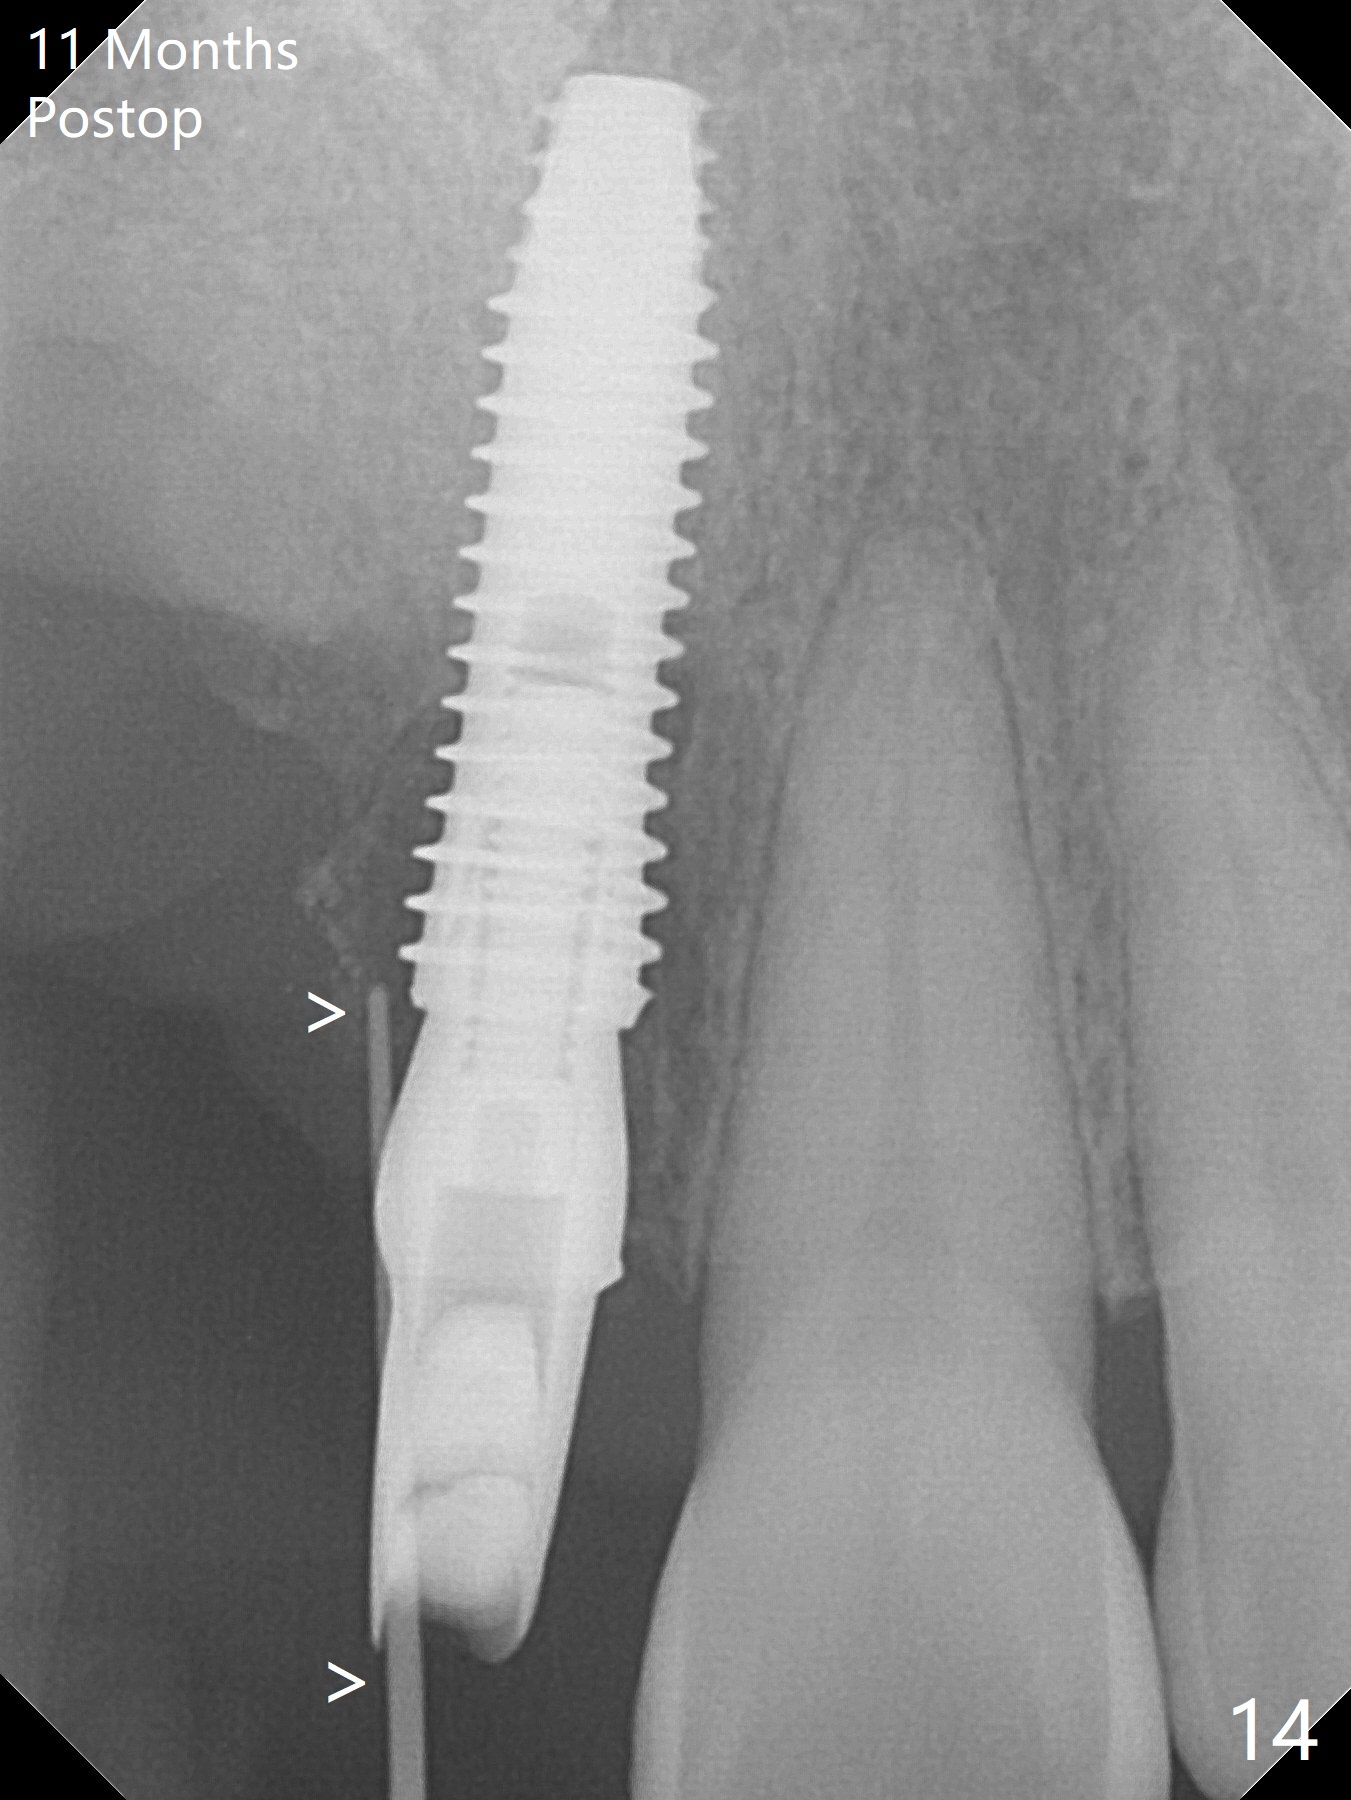

An asymptomatic erythema develops at #8 10 months postop (Fig.12 *). A fistula forms 11 months postop (Fig.13 < ) and is associated with implant thread exposure (Fig. 14 >, as compared to Fig.2). It appears that bone graft and possible block graft are needed with PRF after debridement with Titanium brush.